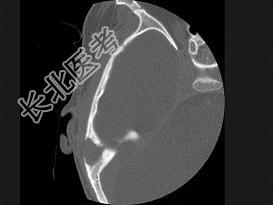

- 单项选择题女性,17岁, 右耳乳突区隐痛,右耳后乳突区出现包块, 逐渐增大,CT检查如图所示, 请选择最可能的 ( )